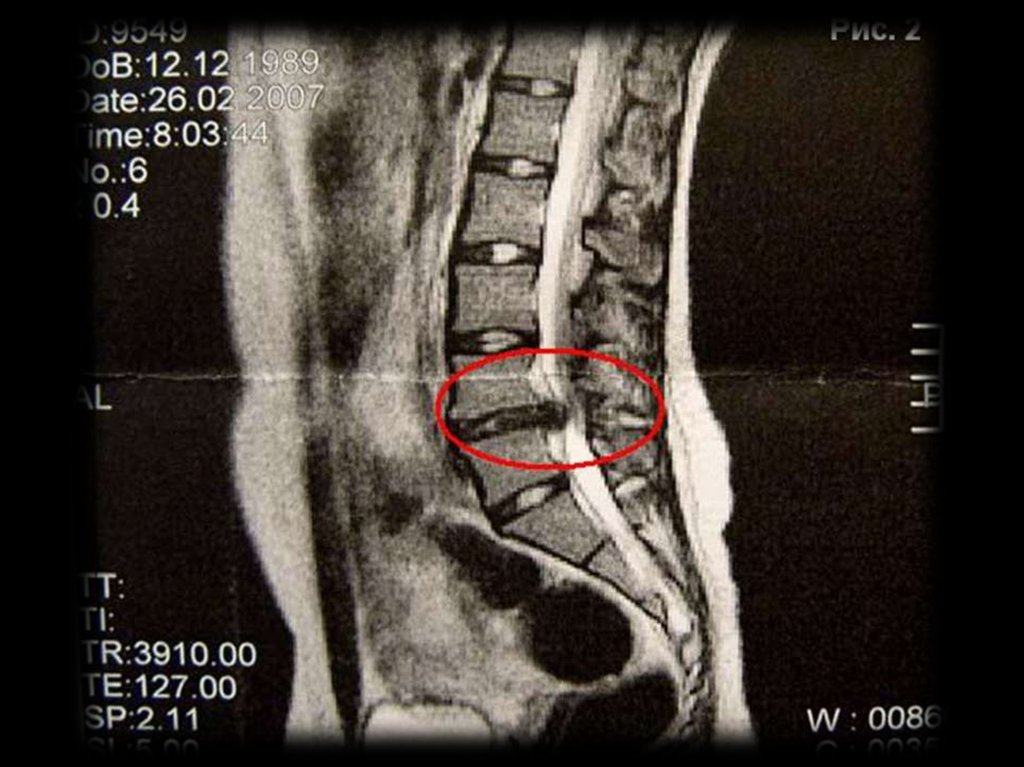

Грыжа диска

Грыжа диска – выпячивание диска за края линии,

соединяющей тела позвонков более 3 мм.

Выпячивание

диска

считается

клинически

значимым, если выпячивание занимает больше

25%

переднезаднего

размера

диаметра

позвоночного канала (≈ 10 мм).

Вызывает смещение задней продольной связки,

компрессию и раздражение спинномозговых

корешков.